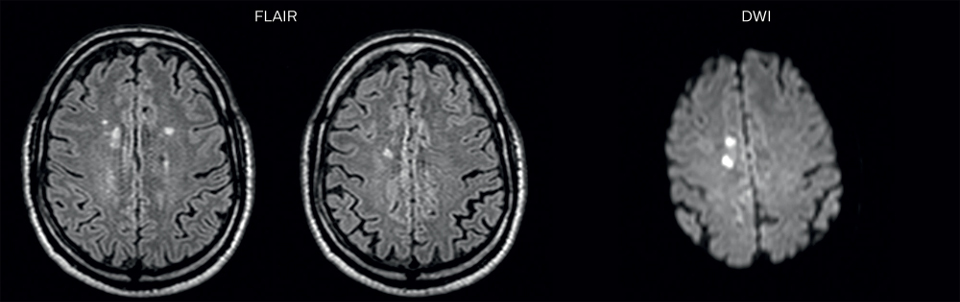

On FLAIR images we can see some nonspecific high signal abnormalities in frontal white matter bilaterally. On DWI we can see acute ischemic lesions which appear with high signal intensity. Arrows show vessel wall enhancement which appears concentric and homogeneous in different cerebral territories.

On the routine MR sequences that we did, we could see acute

ischemic lesions. We see them very well on the diffusion images,

where acute ischemic lesions usually appear with high signal

intensity and restricted diffusion. However, the etiology of these

lesions cannot be derived from these images.

An area of restricted diffusion was seen in the anterior cerebral

artery territory and we concluded it was an ischemic lesion. On

MR angiography we can just see if there is stenosis or vessel

occlusion, but it does not provide us information on the etiology

of this kind of lesion.